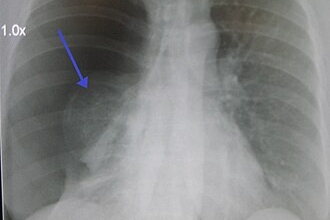

Image d'un important pneumothorax spontané droit

Crédit : James Heilman, MD

Le pneumothorax spontané se caractérise par l'accumulation d'air dans la cavité pleurale, provoquant le décollement du poumon de la paroi thoracique. Les symptômes peuvent inclure des douleurs thoraciques soudaines, une sensation d'oppression, des difficultés respiratoires et, dans certains cas, une paralysie temporaire du bras. Ces manifestations peuvent être confondues avec des signes de stress ou d'autres affections, retardant ainsi le diagnostic.

Dans le cas de Sophia, les douleurs thoraciques ont été initialement attribuées au stress lié à ses études de médecine. Ce n'est qu'après plusieurs consultations et un passage aux urgences que le diagnostic de pneumothorax a été posé. Un examen radiologique a révélé un décollement complet du poumon gauche, nécessitant une intervention chirurgicale d'urgence pour rétablir la fonction pulmonaire.